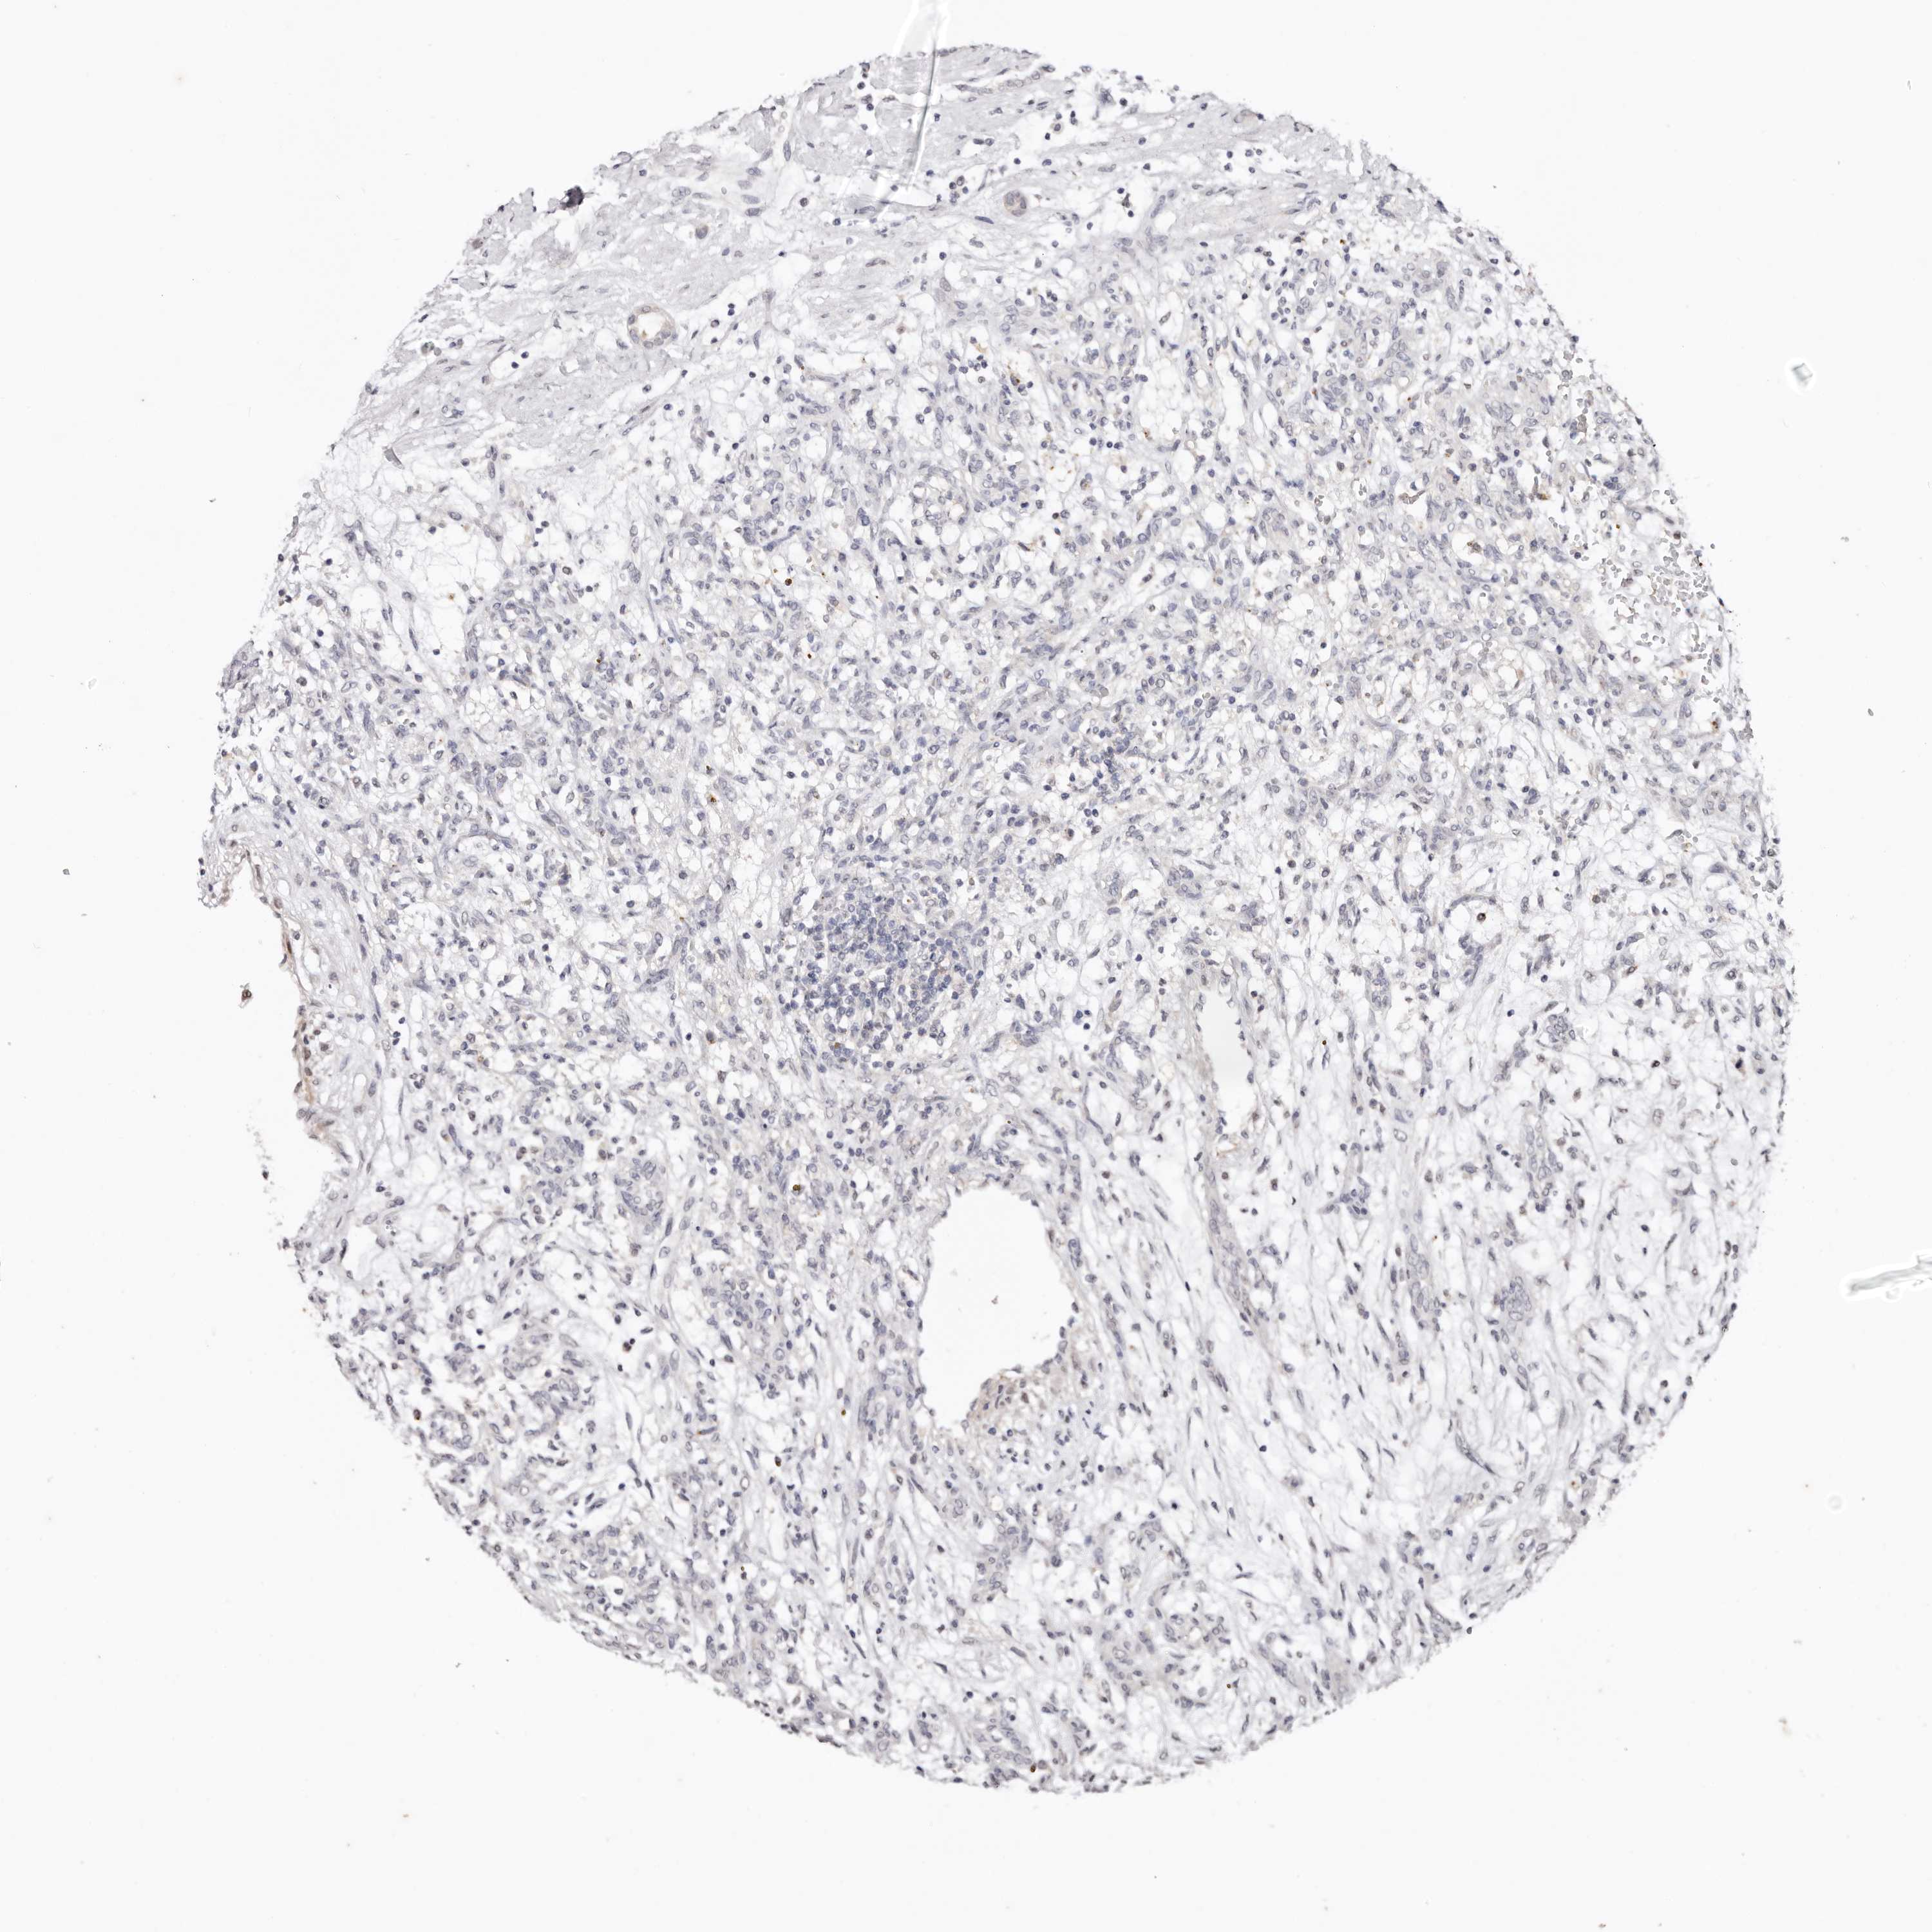

KIDNEY CHROMOPHOBE (TCGA) - Interactive survival scatter ploti

The Survival Scatter plot shows the clinical status (i.e. dead or alive) for all individuals in the patient cohort, based on the same data that underlies the corresponding Kaplan-Meier plots. Patients that are alive at last time for follow-up are shown in blue and patients who have died during the study are shown in red.

The x-axis shows the expression levels (FPKM) of the investigated gene in the tumor tissue at the time of diagnosis. The y-axis shows the follow-up time after diagnosis (years). Both axes are complimented with kernel density curves demonstrating the data density over the axes. The top density plot shows the expression levels (FPKM) distribution among dead (red) and alive patients (blue). The right density plot shows the data density of the survived years of dead patients with high and low expression levels respectively, stratified using the cutoff indicated by the vertical dashed line through the Survival Scatter plot. This cutoff is automatically defined based on the FPKM cutoff that minimizes the p-score. The cutoff can be changed by dragging the vertical line or by entering a cutoff value in the square labeled "Current cut-off".

Under the Survival Scatter plot the p-score landscape (black curve; left axis) is shown together with dead median separation (red curve; right axis). Dead median separation is the difference in median mRNA expression between patients who have died with high and low expression, respectively. It is calculated as follows: median FPKM expression of dead patients with high expression - median FPKM expression of dead patients with low expression. This is intended to aid the user in visually exploring custom cutoffs and the associated p-scores and dead median separation.

Individual patient data is displayed and can be filtered by clicking on one or more of the category buttons on the top of the page. Categories describing expression level and patient information include: high, low, alive, dead, female, male and tumor stages. The scale of the x-axis can be toggled between linear and log-scale by clicking on the "x log" button. Mouse-over function shows TCGA ID, patient information and mRNA expression (FPKM) for each patient.

& Survival analysisi

Kaplan-Meier plots summarize results from analysis of correlation between mRNA expression level and patient survival. Patients were divided based on level of expression into one of the two groups "low" (under cut off) or "high" (over cut off). X-axis shows time for survival (years) and y-axis shows the probability of survival, where 1.0 corresponds to 100 percent.

TYW3 is not prognostic in Kidney Chromophobe (TCGA)

Best expression cut offi

Based on the FPKM value of each gene, patients were classified into two groups and association between prognosis (survival) and gene expression (FPKM) was examined. The best expression cut-off refers the FPKM value that yields maximal difference with regard to survival between the two groups at the lowest log-rank P-value. Best expression cut-off was selected based on survival analysis .

When clicking on this number, the vertical dashed line indicating cut-off, the interactive survival plot, and the Kaplan-Meier curve will be adjusted to show results based on the best expression cut-off.

: 13.89

Median expressioni

Median expression refers to the median FPKM value calculated based on the gene expression (FPKM) data from all patients in this dataset. When clicking on this number, the vertical dashed line indicating cut-off, the interactive survival plot, and the Kaplan-Meier curve will be adjusted to show results based on the median expression.

: N/A

Median follow up timei

Median follow up time refers to the median time (years) after diagnosis with this type of cancer, based on clinical data from all patients in this dataset.

P scorei

Log-rank P value for Kaplan-Meier plot showing results from analysis of correlation between mRNA expression level and patient survival.

N/A

5-year survival highi

5-year survival for patients with higher expression than the expression cutoff.

For melanoma and glioma, 3-year survival is shown.

5-year survival lowi

5-year survival for patients with lower expression than the expression cutoff.

TCGA RNA samplesi

RNA-seq data is reported as average FPKM (number Fragments Per Kilobase of exon per Million reads), generated by the The Cancer Genome Atlas (TCGA) .

Normal distribution across the dataset is visualized with box plots, shown as median and 25th and 75th percentiles. Points are displayed as outliers if they are above or below 1.5 times the interquartile range. FPKM values of the individual samples are presented next to the box plot.

Average pTPM 10.9

Number of samples 64